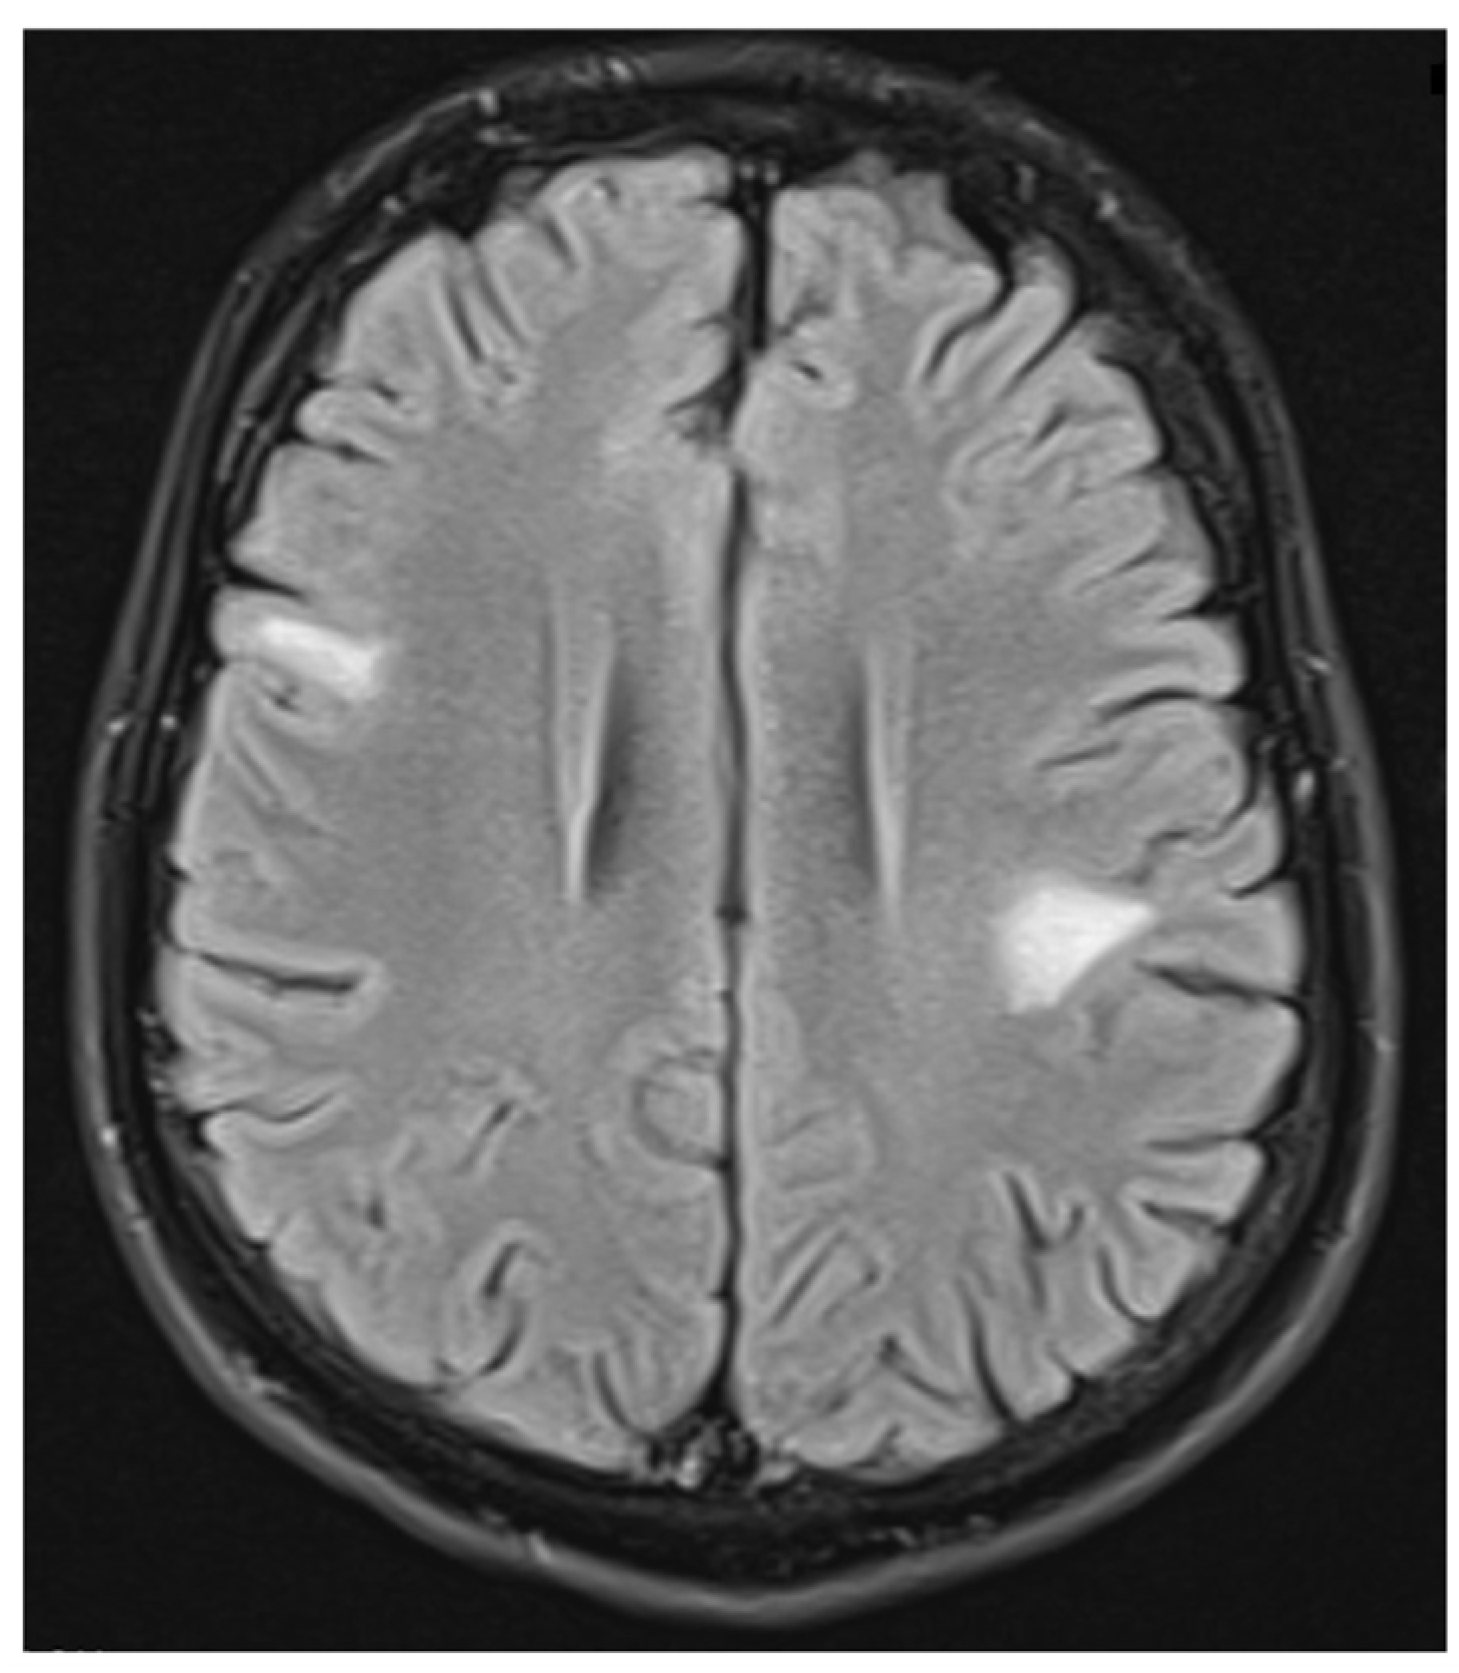

Figure 9.

Transverse FLAIR brain magnetic resonance image showing two new subcortical foci of increased signals: one located in the right frontal lobe measuring 13 × 7 mm and another in the left parietal lobe measuring 19 × 14 mm. (May 2022).

ADEM recurrence was recognized. The patient received immunoglobulins (2.0 g IV). After rehabilitation, an improvement in the neurological condition was observed over the next four weeks. The boy returned to school. Subsequently, he reported visual acuity disturbances in the left eye. Therefore, he was hospitalized in the neurology department. On admission, neurological examination showed horizontal nystagmus, lack of abduction in the right eye, dysarthric speech, and cerebellar syndrome. Brain MRI revealed numerous foci of increased signal on T2-weighted and FLAIR sequences, with the largest one occurring in the right cerebellar hemisphere accompanied by the involvement of the peduncle (Figure 5 and Figure 6) and bilateral involvement of the dentate nuclei of the cerebellum. Foci of increased signals on T2-weighted and FLAIR sequences were also found on MRI of the cervical and thoracic spine, meeting the LETM (longitudinally extensive transverse myelitis) criteria (Figure 7). Moreover, an orbital MRI showed “the left optic nerve was thickened to 3–4 mm, with increased T2 signal intensity indicating inflammation; the optic chiasm and right optic nerve were normal” (Figure 8). Again, positive serum anti-MOG antibodies were found in a clear titer of 1:100, while anti-AQP4 antibodies tested negative. Recurrent MOGAD was diagnosed based on the overall picture, and immunoglobulins were administered (a total dose of 2.0 g IV for five days). Oral azathioprine was included in the chronic treatment at a dose of 2 mg/kg body weight and oral methylprednisolone at a dose of 1 mg/kg body weight. After ten weeks (May 2022), right optic neuritis occurred during an attempt at withdrawing glucocorticosteroids. Methylprednisolone was reintroduced at a dose of 5 × 1.0 g intravenously. An MRI of the head revealed two new subcortical foci: one located in the right frontal lobe measuring 13 × 7 mm and another in the left parietal lobe measuring 19 × 14 mm (Figure 9). Additionally, the right optic nerve exhibited blurred outlines (Figure 10) and an increased signal in the central area, along with a marginally enhancing focus in the middle part of the right optic nerve measuring 2 mm in diameter. An ophthalmological consultation was conducted, revealing color vision deficiencies in the right eye across all axes, with no reading capability in the left eye. An OCT examination showed that the retinal nerve fiber layer (RNFL) in the right eye was normal (higher than a month earlier, suggesting a possible inflammatory process), while the left eye exhibited significantly reduced RNFL and ganglion cell count. Atrophy of the left optic nerve was diagnosed. Based on the clinical presentation, recurrent optic neuritis was diagnosed as a manifestation of another MOGAG, correlating with the onset of right optic neuritis following the discontinuation of methylprednisolone. Therefore, a decision was made to increase the dose of azathioprine to 2.5 mg/kg body weight and to maintain methylprednisolone for the following weeks. After the diagnosis of MOGAD with a typical radiological and clinical picture (ADEM, MDEM, recurrent ON) and the initiation of chronic immunosuppressive treatment, no more epileptic seizures were observed. It was decided to discontinue antiepileptic drugs, starting with gradual valproic acid.